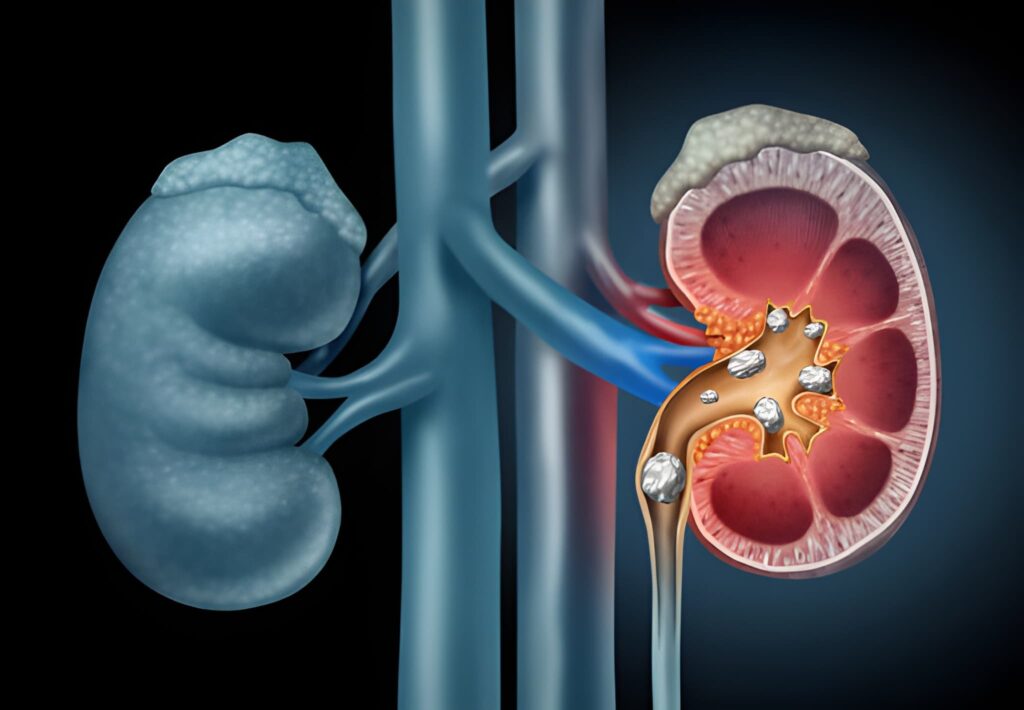

Kidney Stones

Kidney stones are hard mineral deposits that form inside the kidneys. Though often considered an adult issue, they are rising in children due to dietary habits. We focus on “Metabolic Evaluation” to identify the chemical imbalance causing stones.

Warning Signs

- Severe back/side pain

- Blood in urine (Red/Pink)

- Nausea & Vomiting

- Restless crying

Dietary Fixes

- Increase Water Intake

- Limit Processed Foods

- Diet plan according to metabolic work up